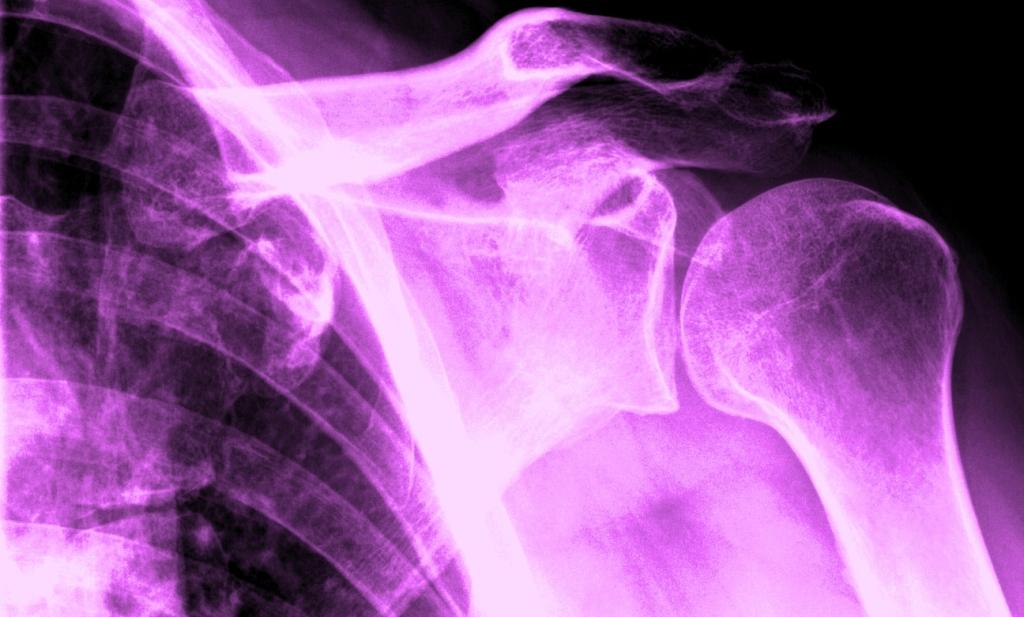

Best of all, the X-ray shoulder views are available, and simple photo-editing software–Paint and Microsoft Office Picture Manager–may be used on the images. Andy Warhol did stuff like this the hard way, back in the day. Longer ago, Robert Rauschenberg had to content himself with light-reactive paper and bright, bright light for some white-on-blue skinscapes of him and his companion. But now–colorizing, brightness&contrast, data compression and many other image-manipulative techniques are easy as pie, funfunfun, and available with the latest operating systems!

So here are four shoulderscapes. If time were not of the essence I would have happily spent another several hours playing with the image; alas, time is scarce. These four, though, demonstrate how color, contrast and cropping of the same subject matter might yield four quite different visual payoffs.